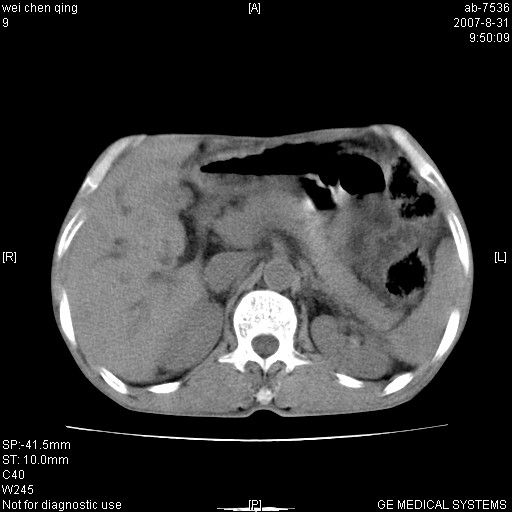

以下是引用zyyzzy在2007-8-31 14:34:00的发言:[br]该病人肝内胆管扩张,胆囊及胆总管未见明显扩张。在倒数第9层图像上可看到左右肝管结合部(肝总管)有软组织影,此处应薄层扫描。考虑肝总管占位(ca)、腹水。[br]